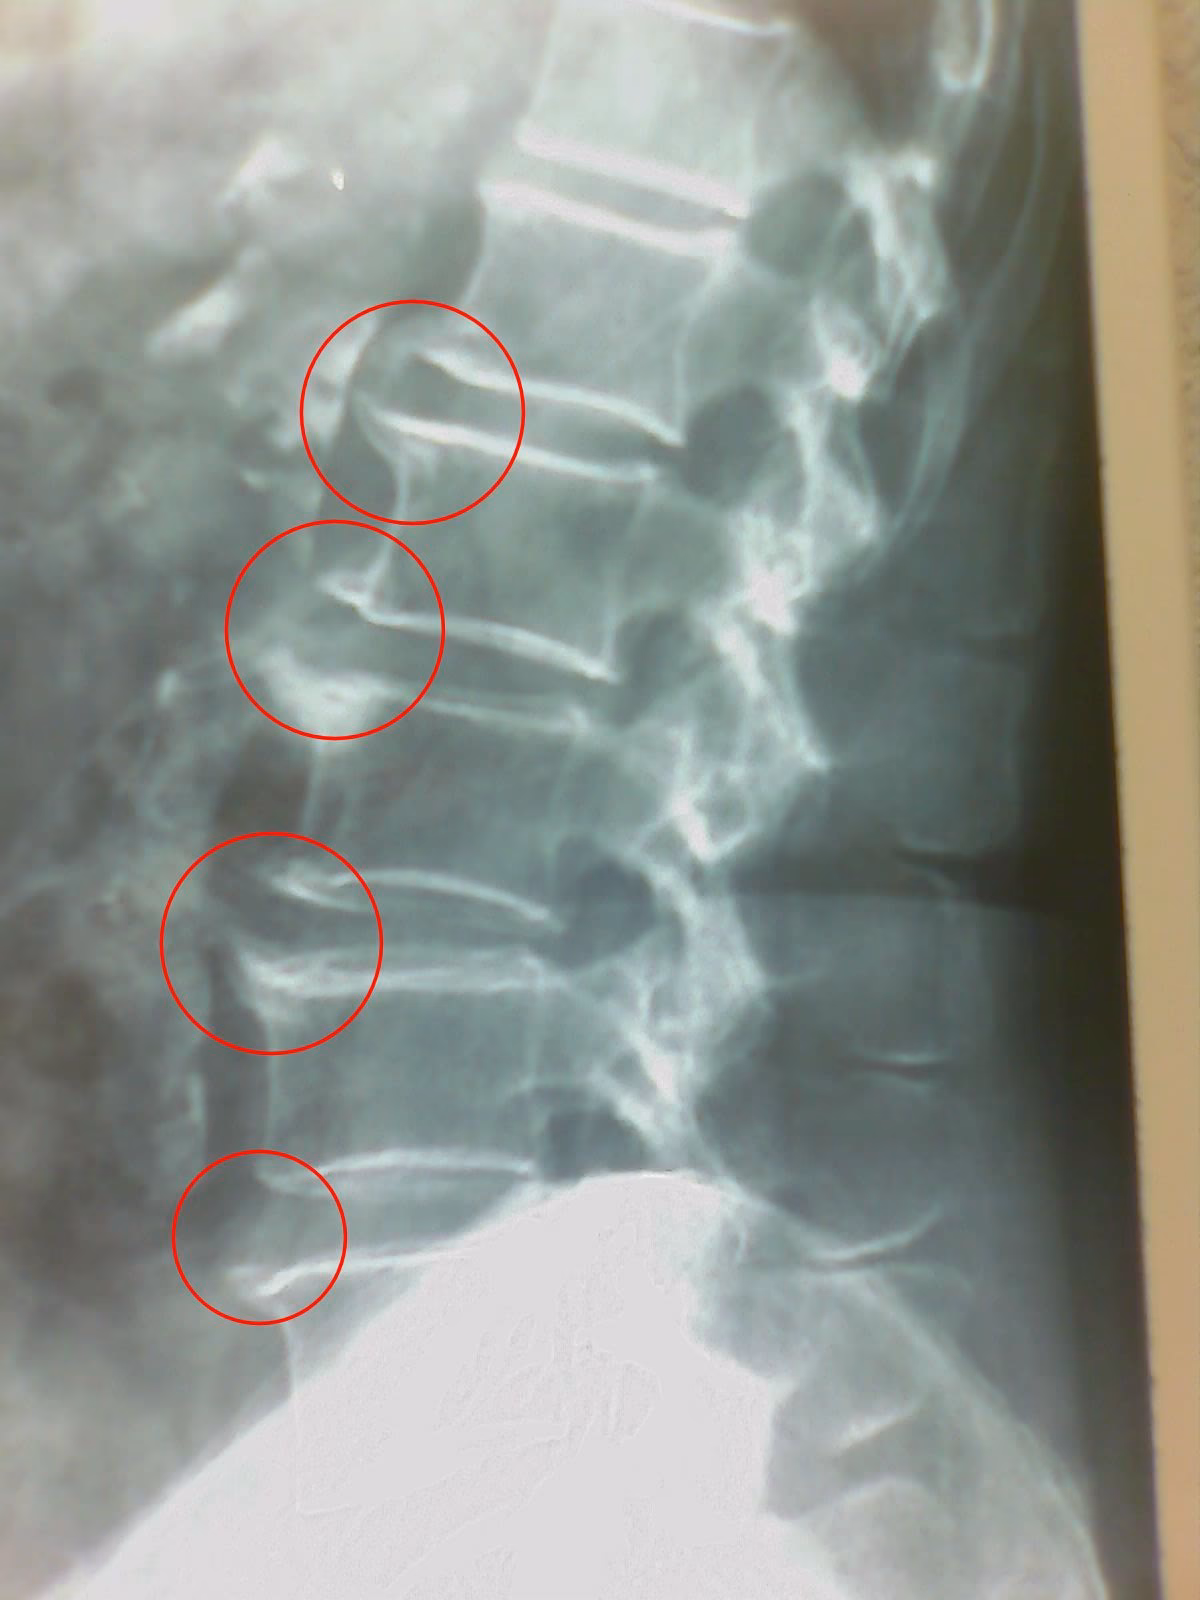

Los osteofitos son proyecciones óseas pequeñas y lisas que se desarrollan a lo largo de los bordes de los huesos. En la columna cervical, suelen formarse en los bordes de los cuerpos vertebrales o en las articulaciones facetarias. Su formación está a menudo relacionada con cambios degenerativos en la columna, como la osteoartritis o la enfermedad degenerativa del disco. El cuerpo intenta 'reparar' o estabilizar las áreas afectadas depositando calcio, lo que lleva a la formación de estos espolones.

- Compresión Nerviosa (Radiculopatía Cervical): Si un osteofito crece hacia el canal espinal o los forámenes intervertebrales (los orificios por donde salen los nervios de la médula), puede presionar las raíces nerviosas. Esto puede causar dolor que se irradia hacia el hombro, el brazo, la mano o los dedos, así como entumecimiento, hormigueo o debilidad muscular en esas áreas.

- Compresión de la Médula Espinal (Mielopatía Cervical): En casos más severos y menos comunes, un osteofito voluminoso puede comprimir la propia médula espinal. Esto es una condición más grave que puede afectar la función de todo el cuerpo por debajo del cuello, manifestándose con problemas para caminar, pérdida de equilibrio, debilidad en las piernas, problemas de control de esfínteres y déficits motores o sensoriales más generalizados.